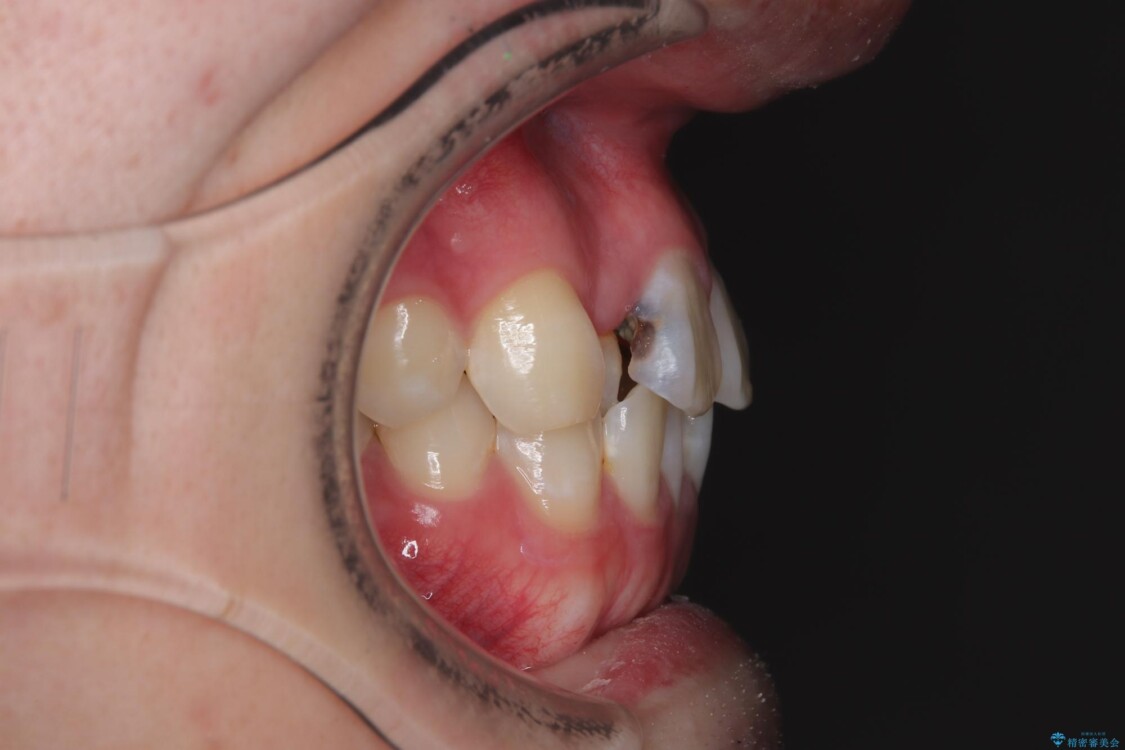

「歯並びがデコボコしていて、上下の中心がズレているのが気になる…」という悩みで来院された患者さまの症例をご紹介します。

初診時の状態

・上下ともに歯がきれいに並びきらず、がたつきが見られました。

・上下の前歯の中心(正中)がずれています。

・特に上顎の幅が狭いため、下顎の歯列も内側に入り込み、歯が並ぶスペースが不足していました。

治療前

• 1年でここまで変わる!歯列のがたつきと正中のズレを改善した矯正治療(メタルブラケット×MARPE) 治療前画像